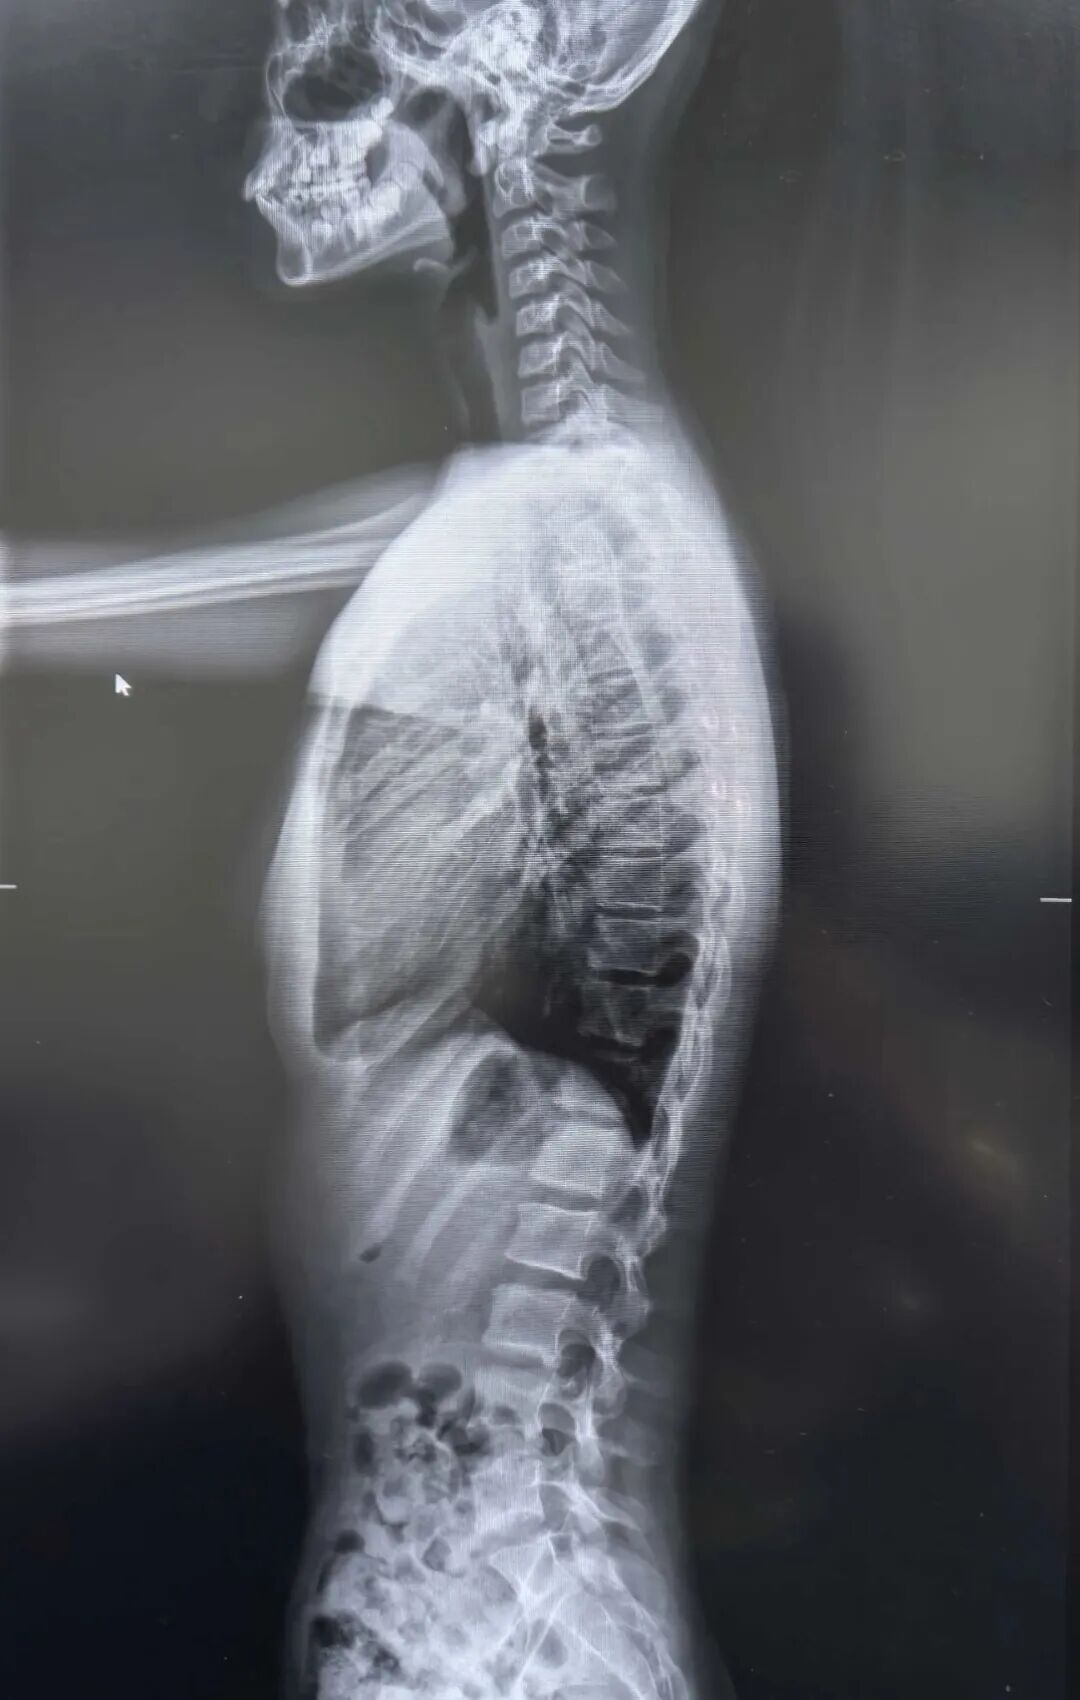

下面让我们一起来详细了解一下“西门子Ysio Max”探测器吧!一、核心技术优势Ysio Max探测器通过创新设计与智能功能,在临床应用中展现出显著优势:1.创新探测器设计:针对性设计的探测器,提升灵活性与适用性。静态MAX(17×17英寸通用探测器):覆盖常规检查场景,适用性广。2.智能操作优化功能:MAXalign实时角度显示:实时显示探测器与X射线管角度,快速对准减少辐射暴露,提升检查效率;探测器触摸显示屏:集成关键信息显示与参数调整功能,简化操作流程,降低人为误差。3.长骨全景成像技术:支持高精度长骨拼接成像(拼接准确、速度快),适用于测定负重骨骼生物力线、脊柱侧凸角等复杂临床场景。

二、成像质量表现Ysio Max探测器通过技术优化,在常规及复杂场景中均能提供优质影像:1.高分辨率与细节捕捉:配备新一代九百万像素平板探测器,显著提升图像分辨率,满足高精度诊断需求。2.技术优化提升质量:钻石窗技术:减少干扰,增强影像对比度与清晰度;碘化铯材料探测器:高效转换X射线信号,提升成像准确性;16比特灰阶:呈现更丰富灰度层次,辅助精准识别病变细节。3.复杂场景稳定性:长骨全景成像技术在骨骼生物力线测定等场景中表现稳定,图像清晰可靠,为手术提供关键依据。